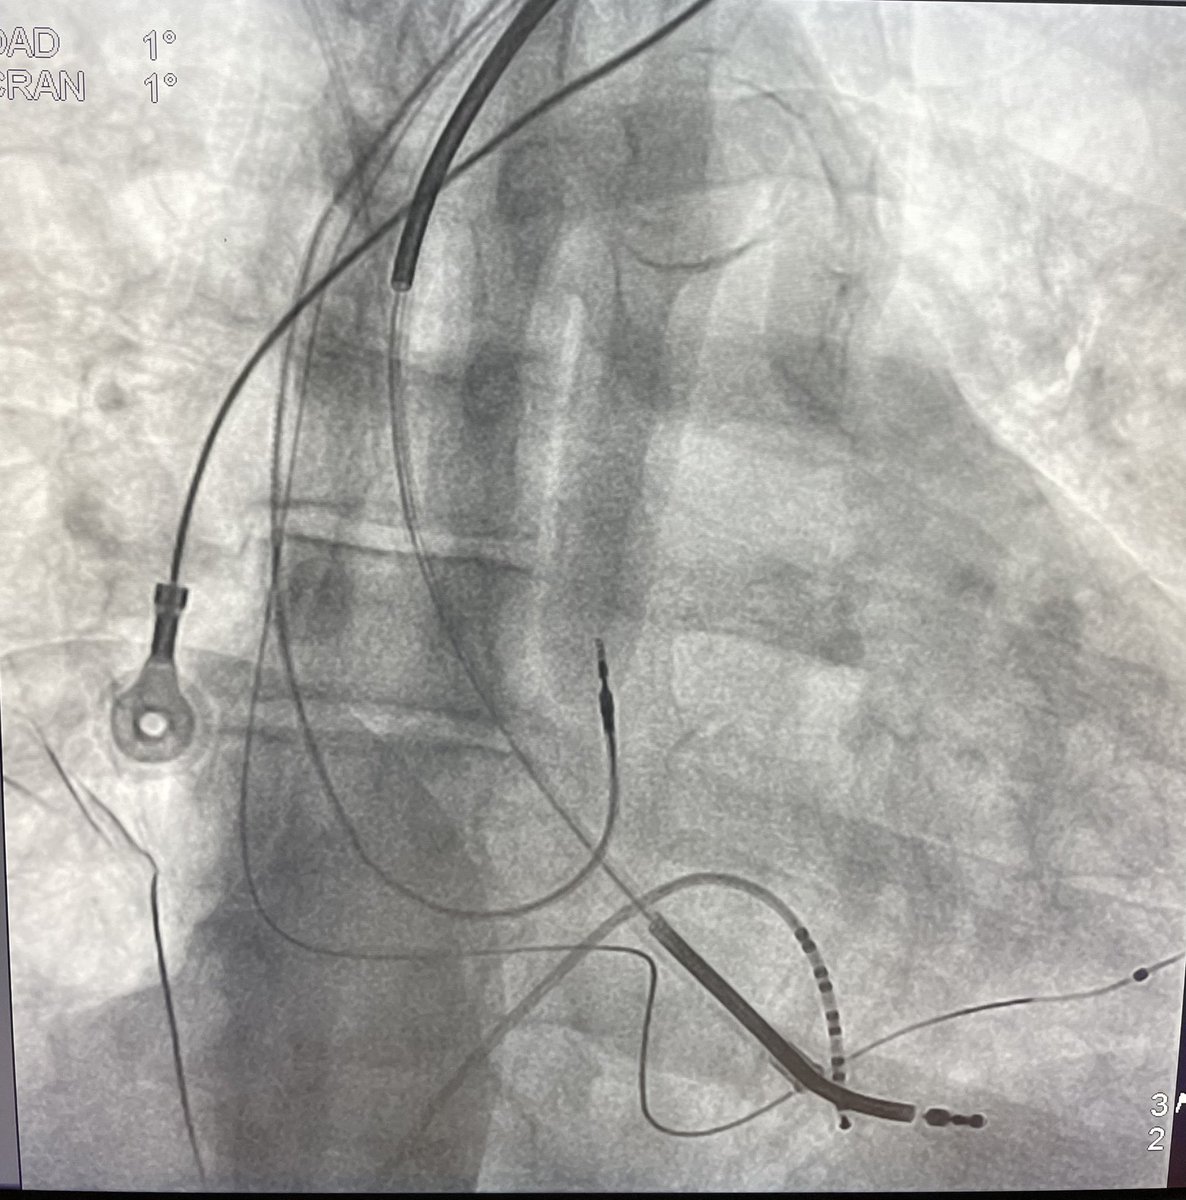

Always loving collaboration with my buddy @FellowEP . Today we did, to the best of our knowledge, the first ISP-LV access in Chile. To tackle a VT storm with mechanical AV and MV. @hhuang123 @DrRoderickTung @Dr_Santangeli @andresenriqueza @ABeaser @gauravaupadhyay